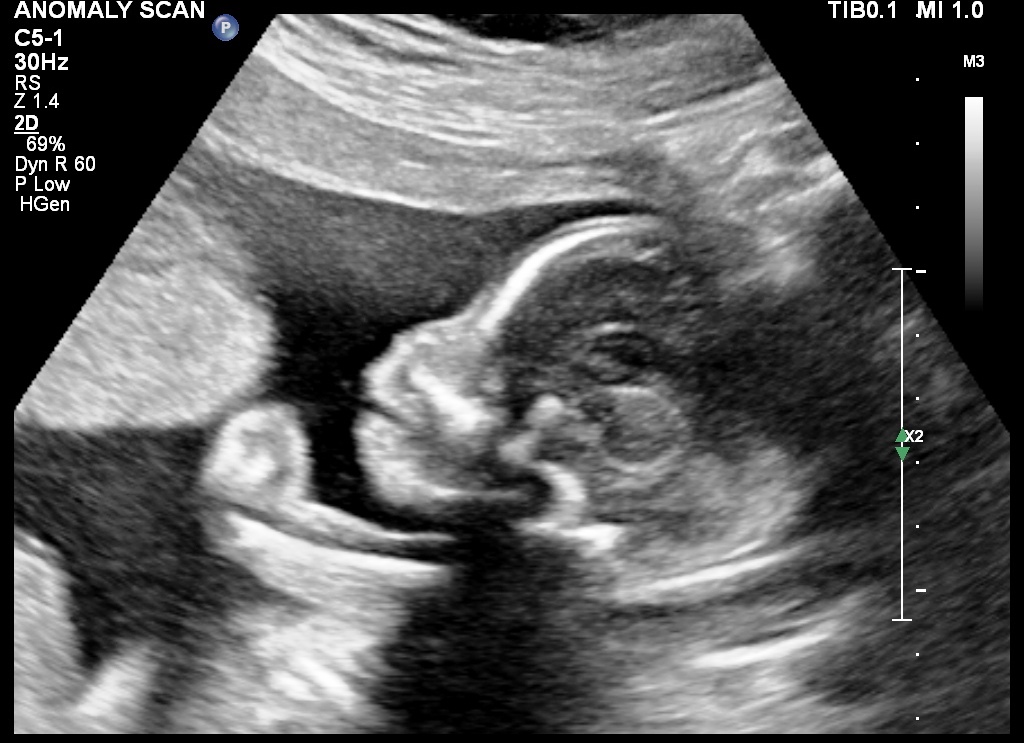

The Obstetrician may ask for a routine ultrasound scan at any stage of gestation, particularly if adequate follow up of the pregnancy has not been done, or if the patient has recently registered with the obstetrician.